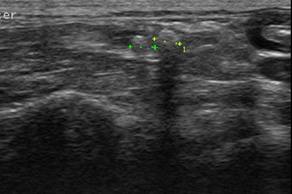

主訴:半年前からたびたび血尿が見られ他の病院で抗生剤と皮下点滴の治療を行っており、治療をやめるとすぐに再発するとのことで当病院に精密検査で来院されました。すぐに検査を行ったところレントゲン検査にて左右尿管に3?4mm程度の小さい尿管結石が認められ、超音波検査では左右尿管とも尿管結石により閉塞している(水尿管)所見が認められ、腎臓内にも尿の貯留(水腎症)が認められました。

今回の検査にて血尿の原因は尿管結石および水腎症によるものと診断しました。この猫ちゃんは残念ながら両方の尿管が結石によって詰まっていたため、